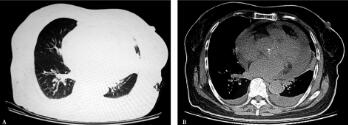

5.胸部CT(2012年8月13日):两肺支气管血管纹理束增多、紊乱,左肺上叶多处片状影及索条影(与2012年6月20日比较未见变化)。双侧胸腔积液,心脏影增大,心包内可见积液(图2A肺窗、B纵隔窗)。

图2

患者第一次入院诊断“社区获得性肺炎”,经合理规范抗感染治疗病情好转,体温平稳1个月余,再次发热,伴进行性呼吸困难,心脏杂音较前增强。应考虑以下问题:①是否再发肺部感染导致发热?是否存在特殊病原体或耐药菌感染?②是否存在肺外感染病灶?尤其感染性心内膜炎?③是否为非感染性疾病——肿瘤或结缔组织疾病?患者再次发热,呼吸系统症状不明显,胸部影像学未发现新的病灶,可除外肺部感染。再次入院查体发现心脏杂音较前增强,结合患者进行性加重的呼吸困难,胸部CT提示心影增大、双侧胸腔积液,临床高度疑诊感染性心内膜炎,进一步复查心脏彩超。D-二聚体进行性升高,需要再次评估肺血栓栓塞症可能性。患者无静脉血栓诱因,呼吸困难原因首先考虑心脏疾病,即肺血栓栓塞症临床评估仍为低度可能。

评价:第一次入院时社区获得性肺炎的诊断是合理的,且经过规范抗感染治疗病情好转,也使CAP诊断得到进一步“验证”,似乎“合情合理”。但患者一月后的再次发热和体格检查以及辅助检查结果,似乎推翻了“原本已明确”的首次出院诊断。诊治过程并没有按照我们预想的进行,病情出现了意外的变化,就像我们无意间走上了“歧路”,回不到预想的终点。这时候感到很迷茫,该怎么办呢?最重要的就是要找到这条“歧路”的起点位于哪个症结,有了这个突破点,很多问题就可以迎刃而解了。这个病例的新突破点就是心脏彩超。